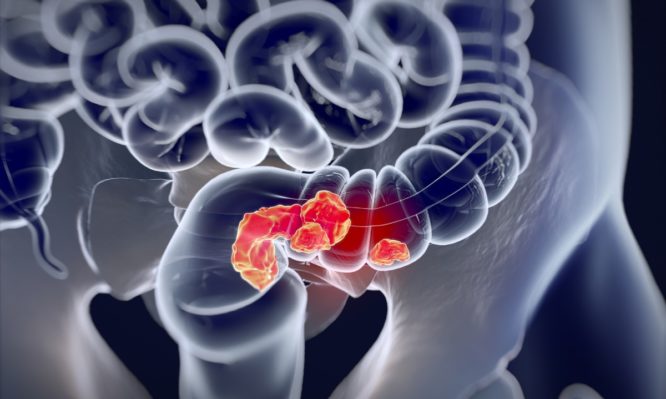

TaTME: Η αιχμή του δόρατος στη χειρουργική θεραπεία του καρκίνου ορθού

Υπάρχουν όμως περιπτώσεις που, ακόμα και με τη χρήση όλων αυτών των τεχνικών, η χειρουργική θεραπεία του καρκίνου του ορθού παραμένει πολύ δύσκολη. Σε περιπτώσεις ασθενών με όγκο που βρίσκεται πολύ χαμηλά στο ορθό, με στενή πύελο, ή με παχυσαρκία, η πλήρης εξαίρεση του οργάνου μαζί με το λίπος που το περιβάλλει γίνεται έως και αδύνατη. Κάτι τέτοιο αυξάνει σημαντικά την πιθανότητα για μόνιμη παρά φύσιν έδρα ή/και αποτελεί έναν πολύ κακό δείκτη για την μετέπειτα εξέλιξη της υγείας των ασθενών αυτών.

Για το λόγο αυτό αναπτύχθηκε η διαπρωκτική ολική μεσορθική εκτομή (TaTME). Αφορά σε μια νέα προσέγγιση στους χαμηλούς όγκους του ορθού, κατά την οποία ο χειρουργός κάνει την επέμβαση «από κάτω προς τα πάνω», δηλαδή ξεκινά την εκτομή από τον πρωκτό και επεκτείνεται προς την κοιλία. Το κυριότερο πλεονέκτημα της τεχνικής αυτής είναι ότι προσφέρει στον χειρουργό πολύ καλύτερη οπτική επαφή με τους ιστούς που χειρίζεται, διευκολύνοντας την πλήρη αφαίρεση του ορθού και του περιορθικού λίπους με τρόπο ώστε αυτά να αφαιρεθούν ανέπαφα. Στις περισσότερες περιπτώσεις επιτυγχάνεται η διατήρηση του σφιγκτήρα, όταν αυτό είναι ογκολογικά αποδεκτό, μειώνοντας την ανάγκη για μόνιμη κολοστομία. Η επέμβασηTaTME μπορεί να πραγματοποιηθεί είτε με χρήση λαπαροσκοπικών εργαλείων, είτε με χρήση ρομποτικής πλατφόρμας.